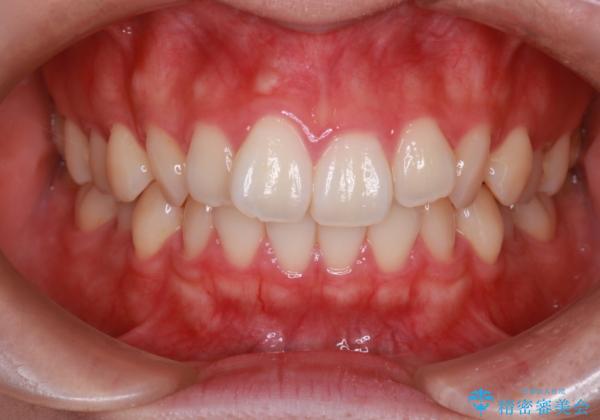

【インビザライン】前歯のねじれを治したい。

- 前歯の凸凹を主訴に来院されました。

スペースを作るために顎間ゴムを使用して、奥歯の遠心移動をおこない配列しました。

奥歯の遠心移動を行うことで、犬歯関係も良い状態に仕上げることができました。